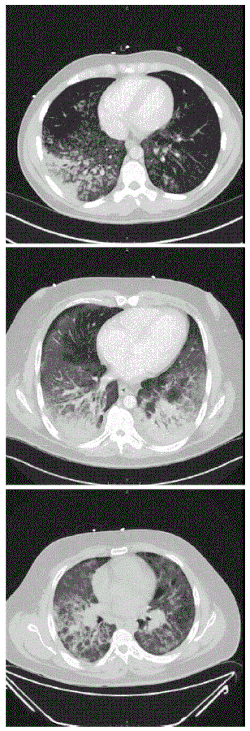

CT scan of the chest showing diffuse lung infiltrates found in three cases of vaping-associated pulmonary injury | |